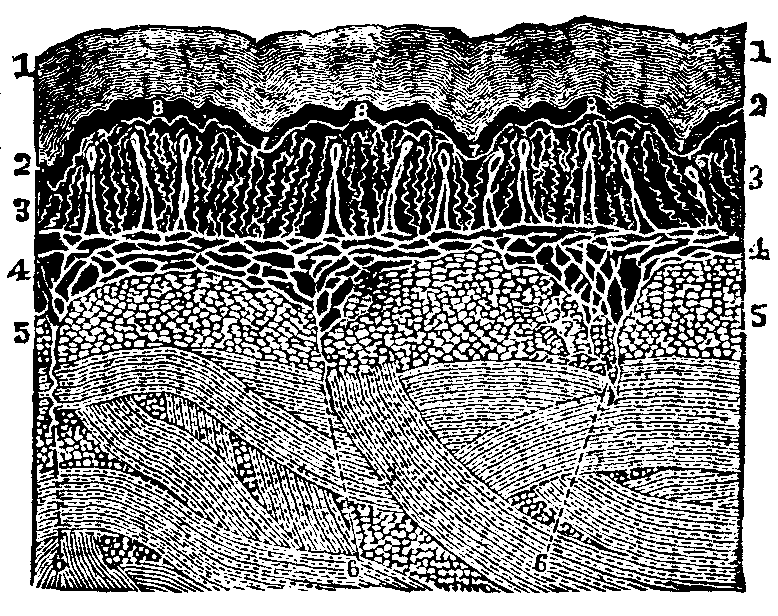

[pg 19]All living bodies are made up of tissues. There is no part, no organ, however soft and yielding, or hard and resisting, which has not this peculiarity of structure. The bones of animals, as well as their flesh and fat, are composed of tissues, and all alike made up of cells. When viewed under a microscope, each cell is seen to consist of three distinct parts, a nucleolus, or dark spot, in the center of the cell, around which lies a mass of granules, called the nucleus; and this, in turn, is surrounded with a delicate, transparent membrane, termed the envelope. Each of the granules composing the nucleus assimilates nourishment, thereby growing into an independent cell, which possesses a triple organization similar to that of its parent, and in like manner reproduces other cells.

Fig. 4. Nucleated cell.

From Goeber. 1. Periphery of the cell, or cell-wall. 2. Nucleus. 3.

Nucleolus in the center.

The Areolar, or Connective Tissue, is a complete network of delicate fibers, spread over the body, and serves to bind the various organs and parts together. The fibrous and serous tissues are modifications of the areolar.

[pg 20]The Nervous Tissue is of two kinds: The gray, which is pulpy and granulated, and the white fibrous tissue. The Adipose Tissue is an extremely thin membrane, composed of closed cells which contain fat. It is found principally just beneath the skin, giving it a smooth, plump appearance.

Fig. 5. Arrangement of

fibers in the Areolar Tissue. Magnified 135 diameters.

The Cartilaginous Tissue consists of nucleated cells, and, with the exception of bone, is the hardest part of the animal frame. The Osseous Tissue, or bone, is more compact and solid than the cartilaginous, for it contains a greater quantity of lime. The Muscular Tissue is composed of bundles of fibers, which are enclosed in a cellular membrane.

Various opinions have been entertained in regard to the formation, or growth, of bone. Some anatomists have supposed that all bone is formed in cartilage. But this is not true, for there is an intra-membranous, as well as an intra-cartilaginous, formation of bone, as may be seen in the development of the cranial bones, where the gradual calcification takes place upon the inner layers of the fibrous coverings. Intra-cartilaginous deposit is found in the vicinity of the blood-vessels, within the cartilaginous canals; also, there are certain points first observed in the shafts of long bones, called centers of ossification. These points are no sooner formed than the cartilage corpuscles arrange themselves in concentric zones, and, lying in contact with one another, become very compact. As ossification proceeds, the cup-shaped cavities are converted into closed interstices of bone, with extremely thin lamellæ, or layers. These, however, soon increase [pg 21]in density, and no blood-vessels can be observed within them.

Fig. 7. Vertical section of

cartilage near the surface of ossification. 1. Ordinary appearance

of the temporary cartilage. 1'. Portion of the same more highly

magnified. 2. The cells beginning to form into concentric zones.

2'. Portion more magnified. 3. The ossification is extending

in the inter-cellular spaces, and the rows of cells are seen resting in the

cavities so formed, the nuclei being more separated than above. 3'.

Portion of the same more highly magnified.